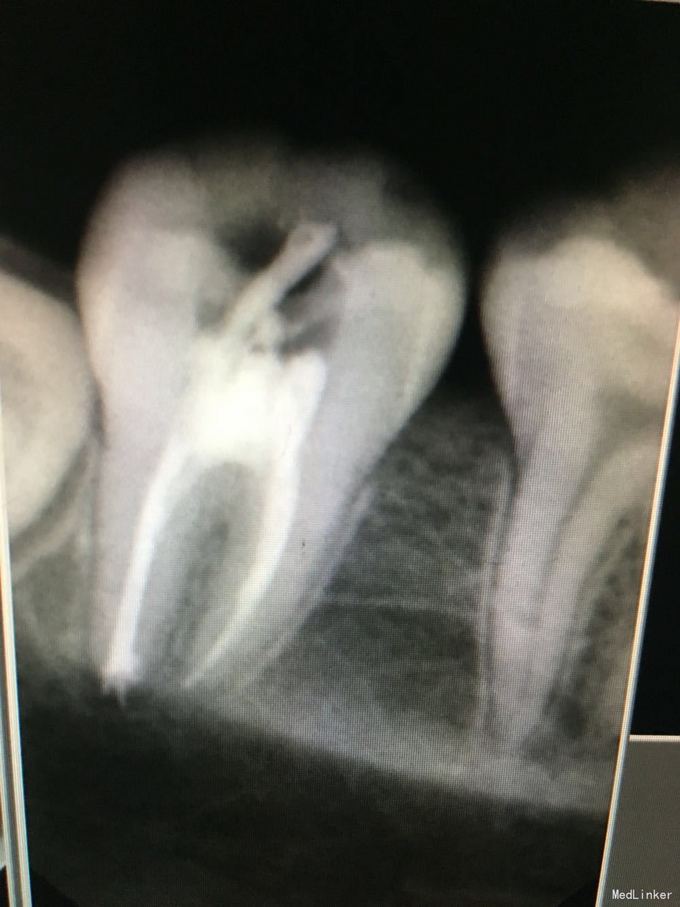

这远中根超充么?

下颌第一磨牙近中3根管远中2根管

远中龋损

根管治疗超充之后怎么补救?